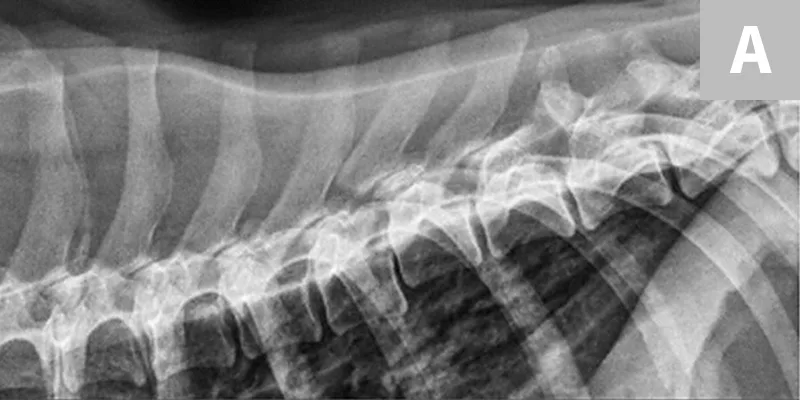

Surgical decompression and stabilization are often recommended for thoracic and lumbar injuries based on the degree of instability and risk for further vertebral column shifting and spinal cord damage. Surgical options include use of positive profile pins or screws with polymethylmethacrylate bone cement, external fixators, and vertebral body plates (Figure 5). Referral to a board-certified neurologist and/or surgeon is recommended for cases in which surgical therapy may be an option. Cats with sacrocaudal luxations may benefit from tail amputation, which removes a source of pain and prevents further traction damage to the sacral nerve roots.

Featured Image

Figure 5

Lateral radiographs taken pre- and postoperatively of a dog after being found in a ditch and presumably hit by a car. (A) There is a T8-T9 subluxation and (inconsequential) T8 spinous process fracture. (B) The subluxation was reduced and stabilized using fully threaded pins, Kirschner wire, and bone cement. The Kirschner wire encircles the pins and is intended to increase the strength of the bone cement. Ideally, these pins would have been placed with more craniocaudal angulation and the construct would have included a third implant spanning the luxation laterally to provide additional support.